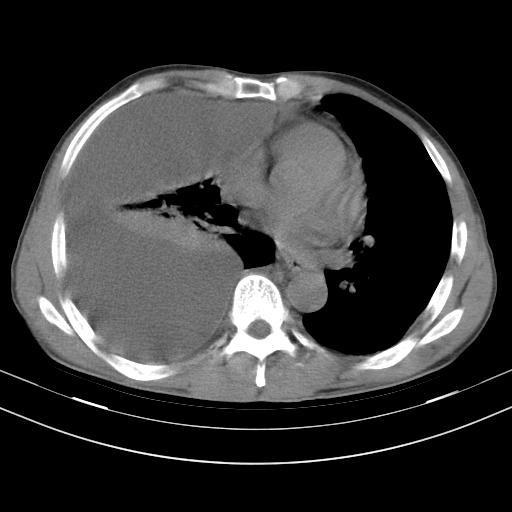

男性,44岁,结核病史多年。现胸闷气短,咳嗽,偶咳血。

1)两肺继发性肺结核伴空洞形成,左肺多发性结核球。2)右侧大量胸腔积液伴右肺部分膨胀不全。3)纵隔淋巴结肿大。

1,双肺多发结节 并空洞影改变, 左侧胸腔积液并部分包裹, 结合原病史首先考虑结核. 但也不除外其它.

2,左侧有一根肋骨陈旧性骨折? 建议追查 .

吉大一院胸水抽检结果:结核性胸水